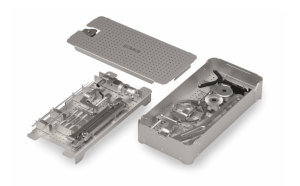

O Navegador Cirúrgico Eximius, é um equipamento de localização espacial em tempo real que rastreia continuamente os instrumentos cirúrgicos e sua relação com as estruturas anatômicas do paciente. Trata-se de um equipamento composto por uma unidade de processamento, sensor de posição, marcadores de referência estática e dinâmica, software de reconstrução tridimensional de imagens médicas e instrumentais cirúrgicos previamente calibrados.

O módulo básico do Sistema Eximius de Navegação Cirúrgica contempla o sensor de posição, unidade de processamento, marcadores de referência estáticos e dinâmicos, além de instrumentais específicos que permitem a realização de procedimentos de navegação em crânio.